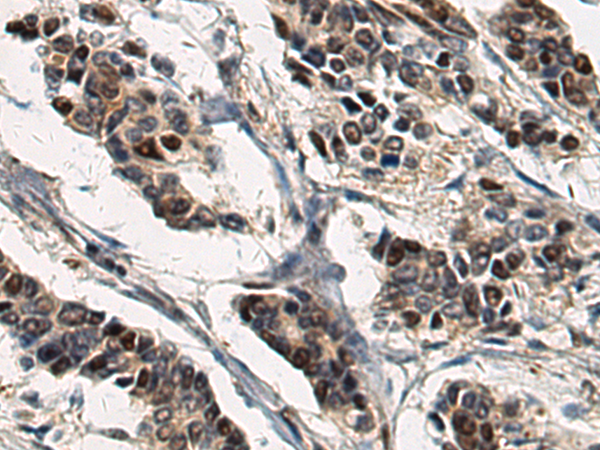

WB, IHC

IHC positive control:

Human ovarian cancer and Human breast cancer; Human esophagus cancer and Human lung cancer

IHC Recommend dilution:

250-1000